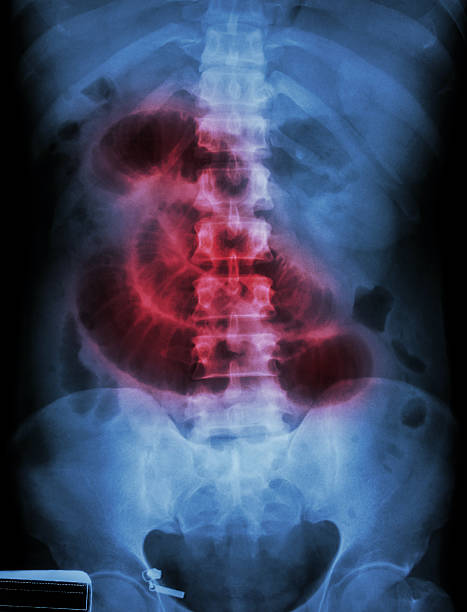

장폐색 증상

복통

장폐색으로 인한 복통은 일반적으로 속이 아프고 발작적으로 오는 통증이 특징입니다. 통증은 복부 중앙에서 시작하여 전체 복부로 퍼지는 경우가 많습니다. 또한 복통과 함께 소화불량, 구토, 식욕부진 등의 증상도 나타날 수 있습니다.